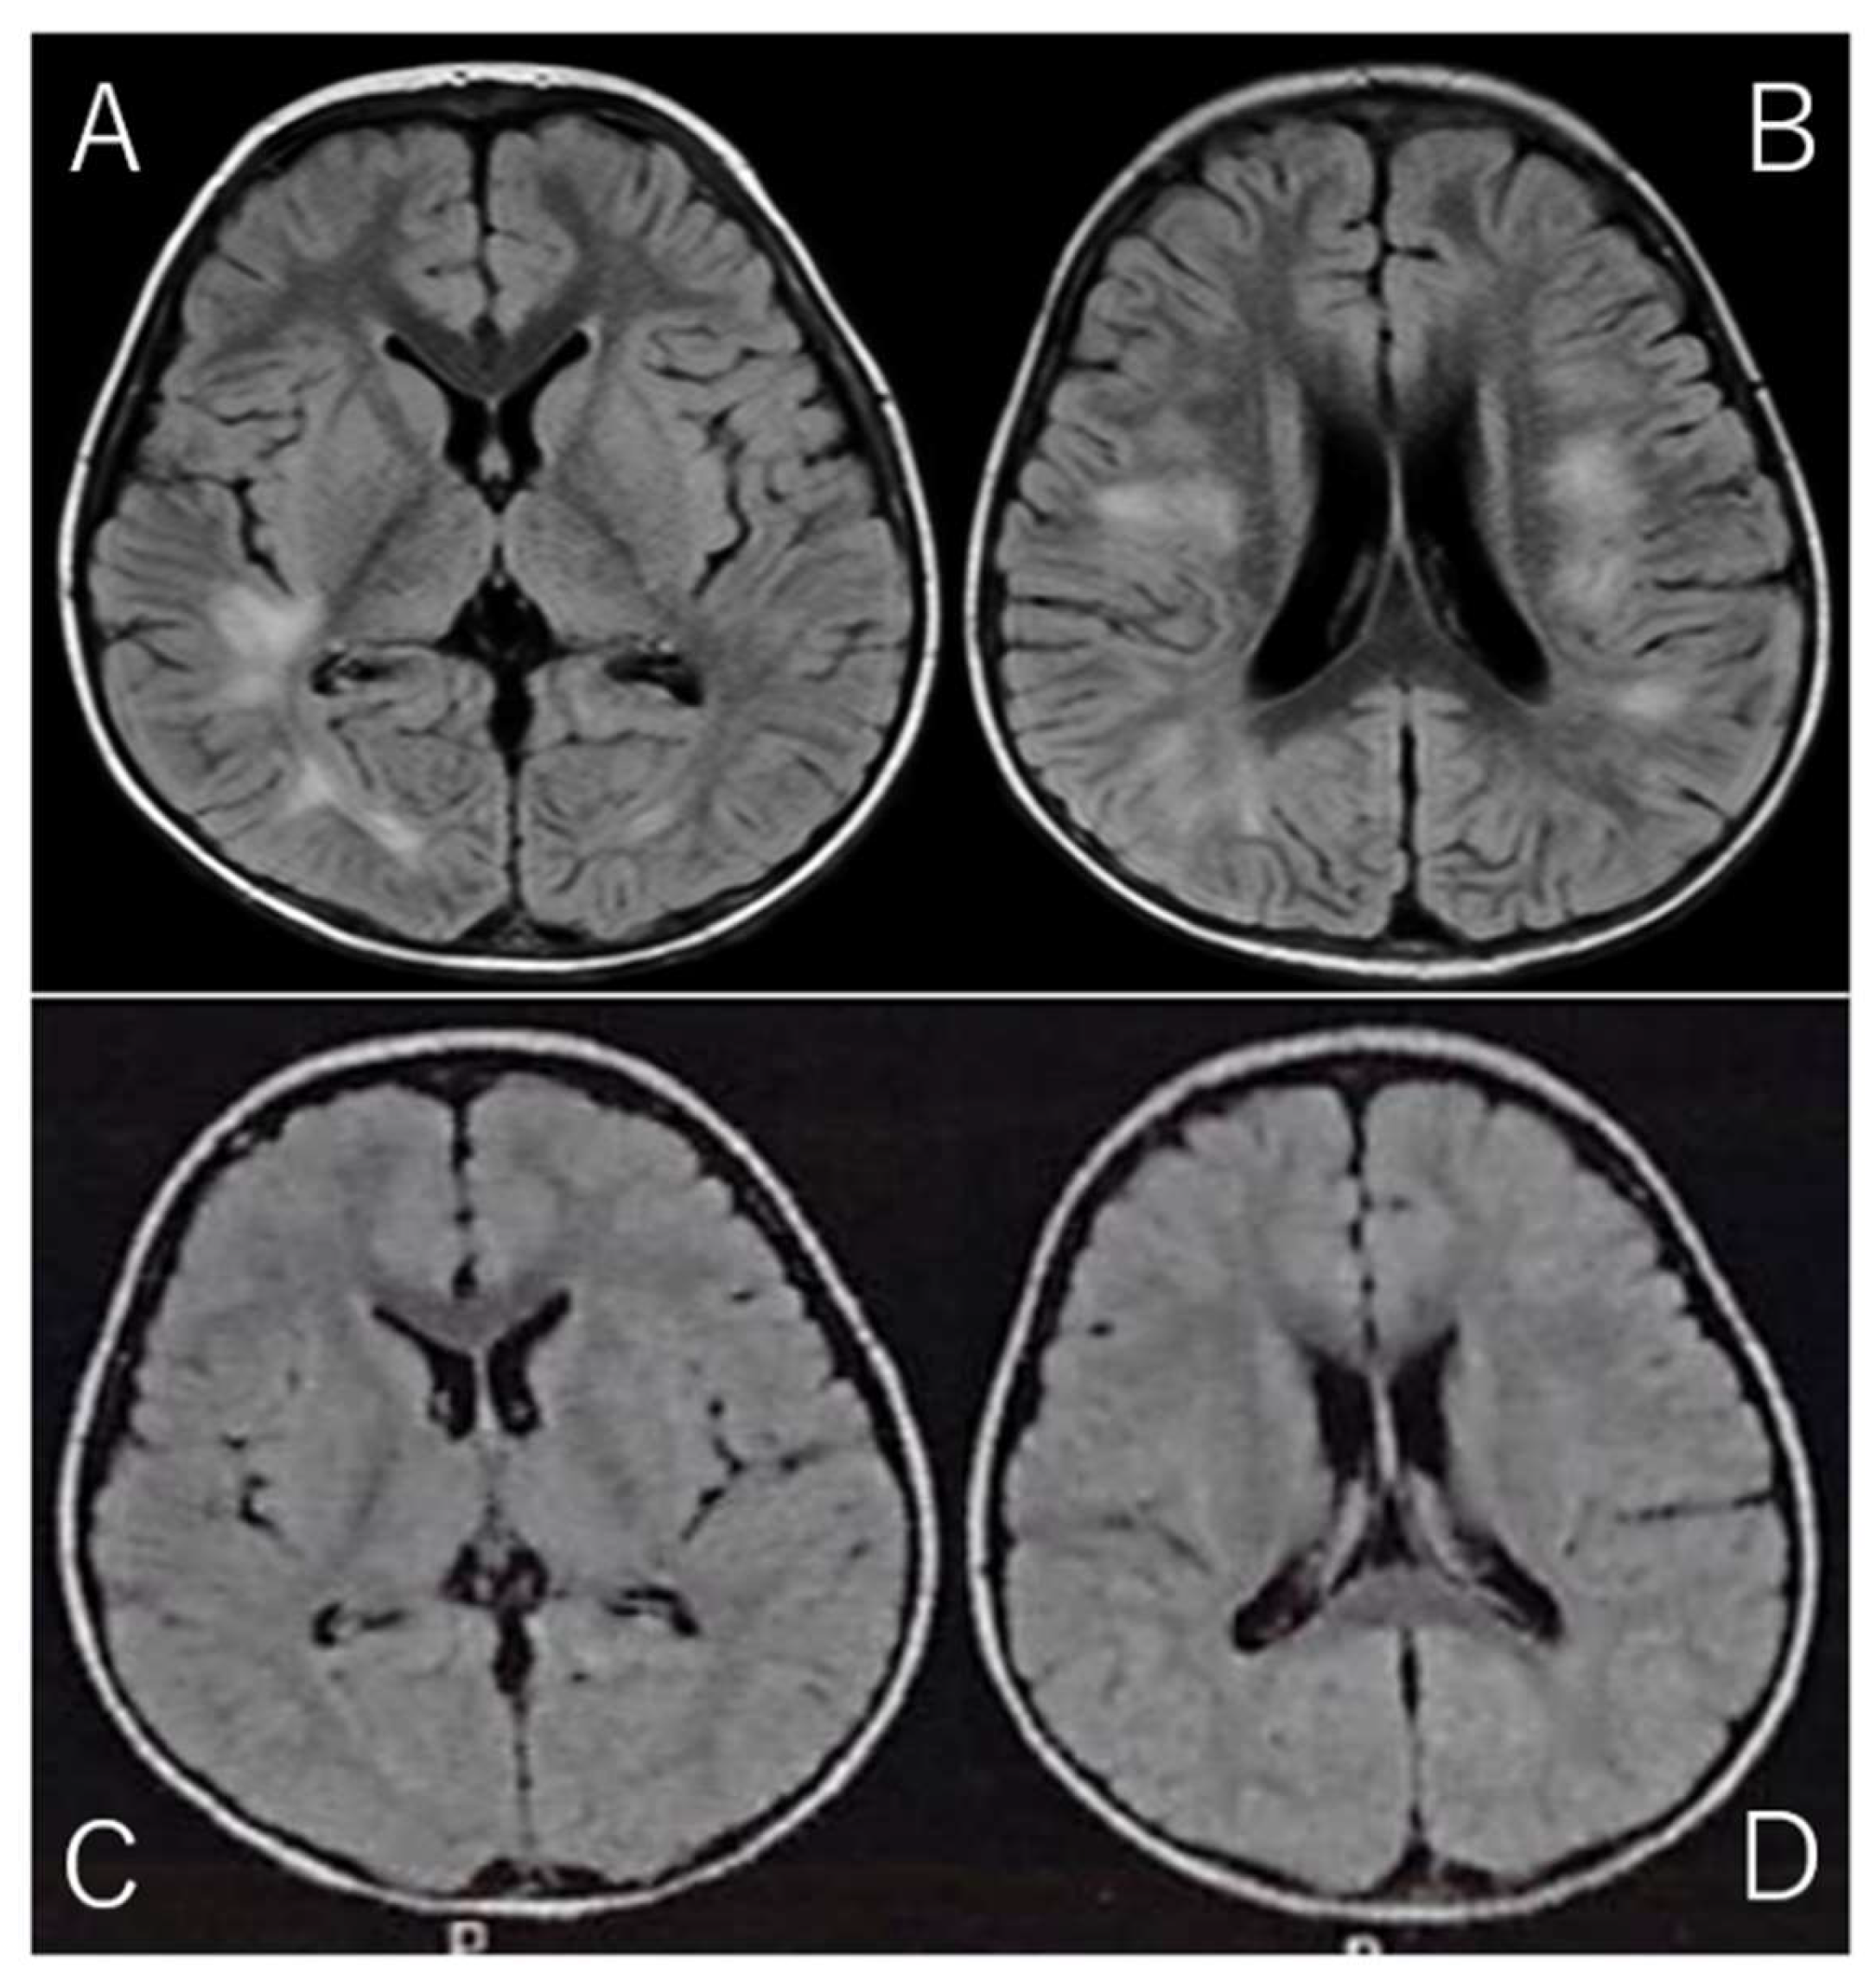

Given the clinical presentation and CSF findings, along with the marked elevation in IL-2R, a diagnosis of acute disseminated encephalomyelitis (ADEM) was suspected. ADEM is a rare but serious autoimmune-mediated demyelinating disorder of the CNS, often triggered by viral infections or vaccinations. The diagnosis was further supported by brain MRI findings, which were obtained using the fluid-attenuated inversion recovery (FLAIR) sequence. FLAIR imaging is particularly useful for detecting abnormalities in the brain's white matter, as it suppresses cerebrospinal fluid signals and highlights areas of high-water content. The MRI revealed high-intensity lesions bilaterally in the periventricular white matter, particularly beneath the cerebral cortex (Fig. 1A/B), which is a classic finding in ADEM. These lesions, indicative of acute demyelination, were consistent with the diagnosis of ADEM, a condition that can present with various neurological deficits, including motor dysfunction, altered consciousness, and in some cases, seizures.

The patient was discharged after a total of 14 days of hospitalization, during which he also underwent physical therapy to address the initial motor difficulties and to support his recovery. Follow-up MRI performed just prior to discharge showed a marked reduction in the high-intensity lesions (Fig. 1C/D), which is consistent with the expected resolution of acute demyelination following appropriate treatment. These MRI findings provided further confirmation of the positive treatment response and the expected recovery trajectory in ADEM cases.

Brain MRI on Admission and Discharge. (Spin Echo Method: Fluid Attenuated Inversion Recovery; FLAIR Axial: TR = 9,000, TE = 104, FA = 150).

A/B: On admission, brain MRI with the Fluid Attenuated Inversion Recovery (FLAIR) sequence revealed high-intensity lesions bilaterally beneath the cerebral cortex, with asymmetrical involvement. FLAIR imaging, designed to suppress cerebrospinal fluid signals, provides enhanced visibility of brain parenchyma abnormalities, particularly those involving edema or inflammation. The bilateral, asymmetrical nature of the lesions suggests a possible systemic or multifocal pathology. These lesions are characterized by abnormal fluid accumulation, which appears bright on FLAIR images due to the suppression of CSF, allowing for better delineation of tissue abnormalities.

C/D: On follow-up MRI at discharge, these lesions had significantly improved, with reduced intensity in the previously affected areas. The reduction in signal suggests a decrease in underlying edema or inflammation, reflecting a positive change in the brain's condition. This improvement highlights the effectiveness of follow-up imaging in monitoring the resolution of abnormalities over time.